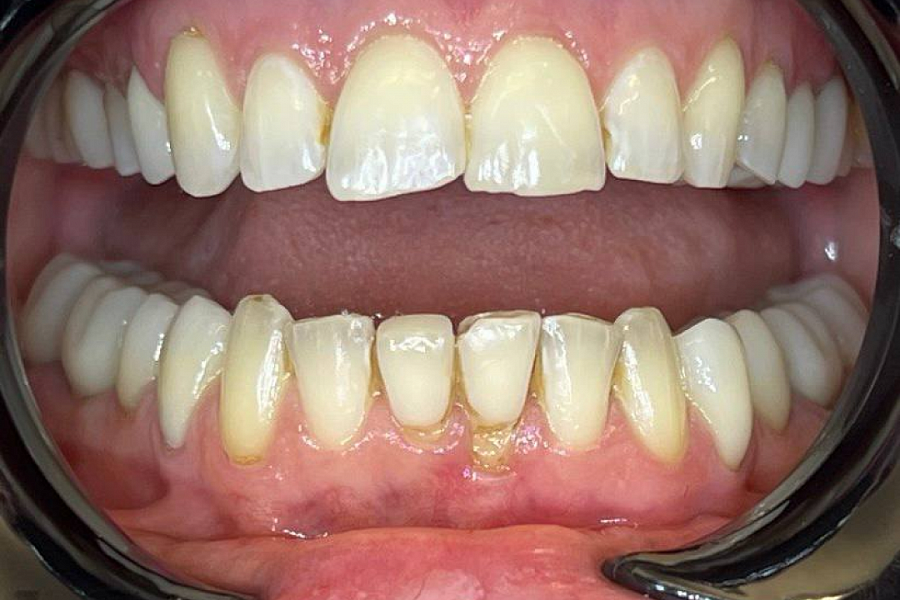

Этапы лечения

Была проведена тщательная диагностика, после чего принято решение о комплексном подходе к лечению.

Сначала было проведена санация полости рта. Затем а ортодонтическое лечение для восстановления высоты прикуса.

С эстетической частью справились за счёт протезирования винирами в естественной форме и в естественном цвете.

Результат получился отличный! Пациентка очень довольна!

Результат лечения